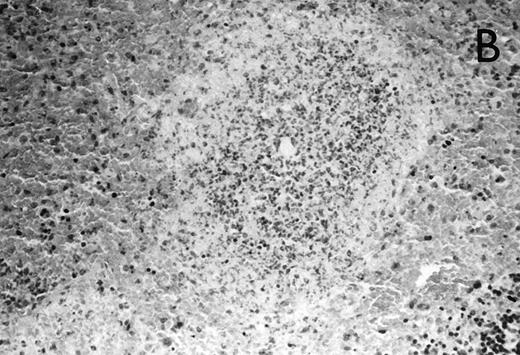

Histology further supported this observation. Control animals showed well-developed pneumonia with abscess formation (Fig3A) in their lungs, but in their livers, only small areas of inflammation with scattered microabscesses and foci of hepatic necrosis were observed (Fig 3B). In contrast, mice pretreated with G-CSF had only mild peribronchitic alterations in their lungs without signs of containment of inflammation such as abscess formation (Fig 4A). Livers and spleens of mice pretreated with G-CSF were severely altered, showing large abscesses which contained massive amounts of bacteria (Fig 4B). In addition, large necrotic areas surrounded by granulocytes were observed in the livers (Fig 4C). When MoAb III/5-1 was administered in addition to pretreatment with G-CSF, almost all changes observed in animals pretreated with G-CSF were reversed: there were only minor bronchial and peribronchial infiltrations by granulocytes (minimal change focal pneumonia), and the livers showed small microabscesses as observed in control mice. When treatment with G-CSF was started at 24 hours after bacterial challenge, a mixed pattern was observed. In the lungs, there was a beginning pneumonic reaction and a moderate perivascular and septal edema. However, in the liver there was almost no difference to the severe alterations observed in mice pretreated with G-CSF: huge abscesses loaded with bacteria joined extended necrotic areas.

(A) Micrograph of lung tissue 48 hours after intranasal infection with 1 × 103 CFU of K pneumoniae B5055 and pretreatment with G-CSF (50 μg/kg sc) at −48 hours, −36 hours, −24 hours, and −12 hours before infection. Peribronchiolar neutrophils without destruction of lung parenchyma. H&E; original magnification ×150. (B) Splenic abscesses in the red pulp containing numerous gram-negative bacilli are found. H&E; original magnification ×370. (C) Confluent hepatic necroses. H&E; original magnification ×150.